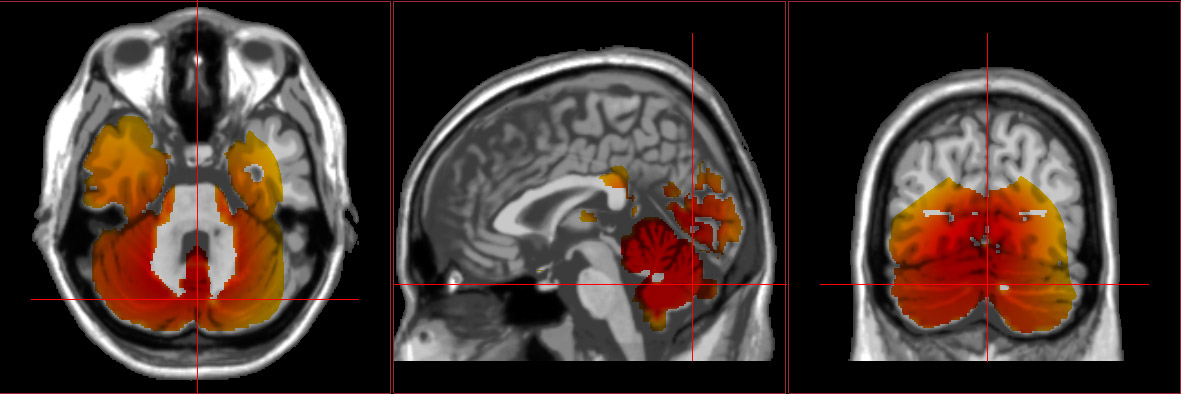

How a head injury affects functioning depends largely on the location, intensity, and frequency of the injuries. QEEGs show an increase in slower brain waves like delta and theta in damaged brain regions. These waves are reparative in nature and are at frequencies essential to cell growth. However, in the case of some injuries, these slower waves can stick around and negatively impact the overall functioning of the brain.

It is especially common to see EEG slowing in the temporal lobes after concussions, regardless of the site of the impact. This observed slowing is thought to contribute to the memory, emotional processing, and language processing problems that many individuals with brain damage experience.

swLORETA brain scan showing a concussion